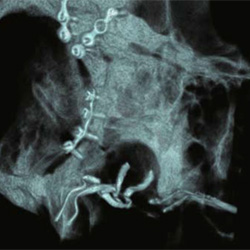

Elektrodenkontrolle nach

Cochlear Implantation